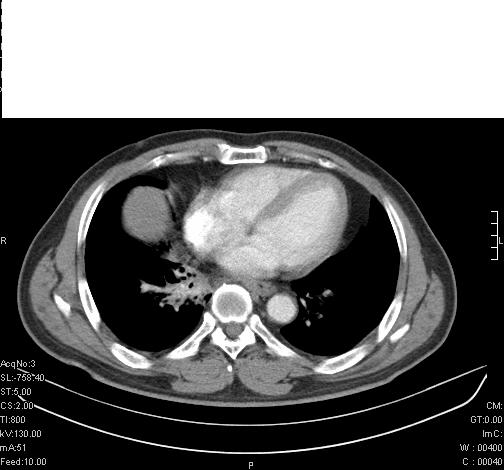

标题: CT6685:右肺阻塞性炎症,增强CT。 [打印本页]

标题: CT6685:右肺阻塞性炎症,增强CT。

前几天,发了患者的平扫片,患者抗炎一周后增强扫描。右中叶病灶吸收明显,但下叶病灶未见明显吸收。右肺门可见结节影,看来凶多吉少

右肺下叶支气管管腔狭窄,管壁增厚,右下肺见斑片状高密度影,考虑右侧肺门中心肺癌伴阻塞性肺炎

右肺下叶散在的斑片状致密影,下叶支气管变窄。考虑:右肺慢性炎症。

右肺下叶支气管壁明显增厚,考虑癌症并阻塞性炎症、肺门淋巴结肿大

考虑右肺癌并阻塞性炎症、肺门淋巴结肿大

右肺下叶支气管壁不规则增厚,右肺下叶有斑片状影分布。考虑右肺中央型肺癌伴右肺下叶阻塞性改变。建议支纤镜检查。平扫比增强较好显示了病变情况。

右主支气管狭窄,管壁增厚。考虑右中心性肺ca伴阻塞性肺炎。

既然抗炎治疗有效,可继续治疗;右肺下叶支气管管腔狭窄,管壁增厚,右下肺见斑片状高密度影,右侧主支气管后见结节影(淋巴结?),肺癌不能排出。